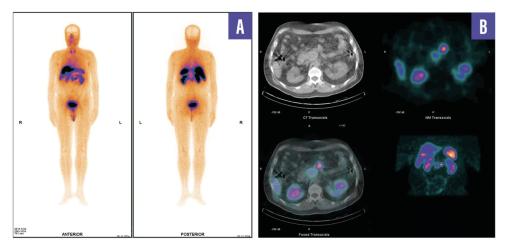

Un homme de 53 ans, sans antécédents, consulte pour des douleurs abdominales diffuses évoluant depuis plusieurs semaines. Le bilan biologique est normal. Une tomodensitométrie abdomino-pelvienne met en évidence une masse rétropéritonéale infiltrante associée à une adénopathie lombo-aortique. La tomographie par émission de positons (TEP-TDM au 18F-FDG) montre un hypermétabolisme léger de la lésion rétropéritonéale, mais l’adénopathie ne fixe pas le FDG (fig. 1). Un foyer hypermétabolique thyroïdien droit est également détecté. Une biopsie échoguidée confirme une tumeur neuro-endocrine digestive bien différenciée de grade 2 (Ki- 67 à 12 %). La scintigraphie au 99mTc-Tektrotyd révèle une fixation intense de l’adénopathie, compatible avec une pathologie neuro-endocrine exprimant les récepteurs de la somatostatine (fig. 2). Un nodule thyroïdien droit conduit à une thyroïdectomie totale, confirmant un microcarcinome papillaire.